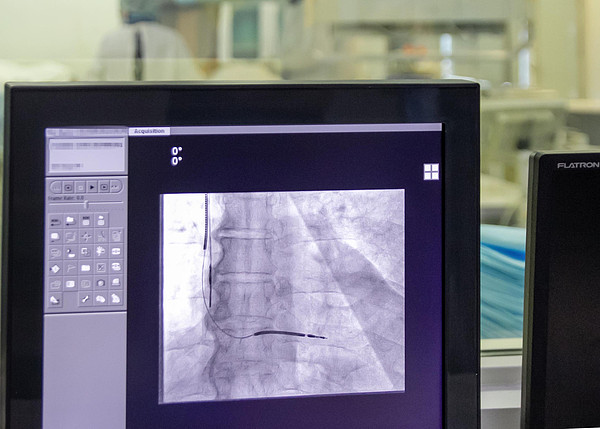

IMG_3164.